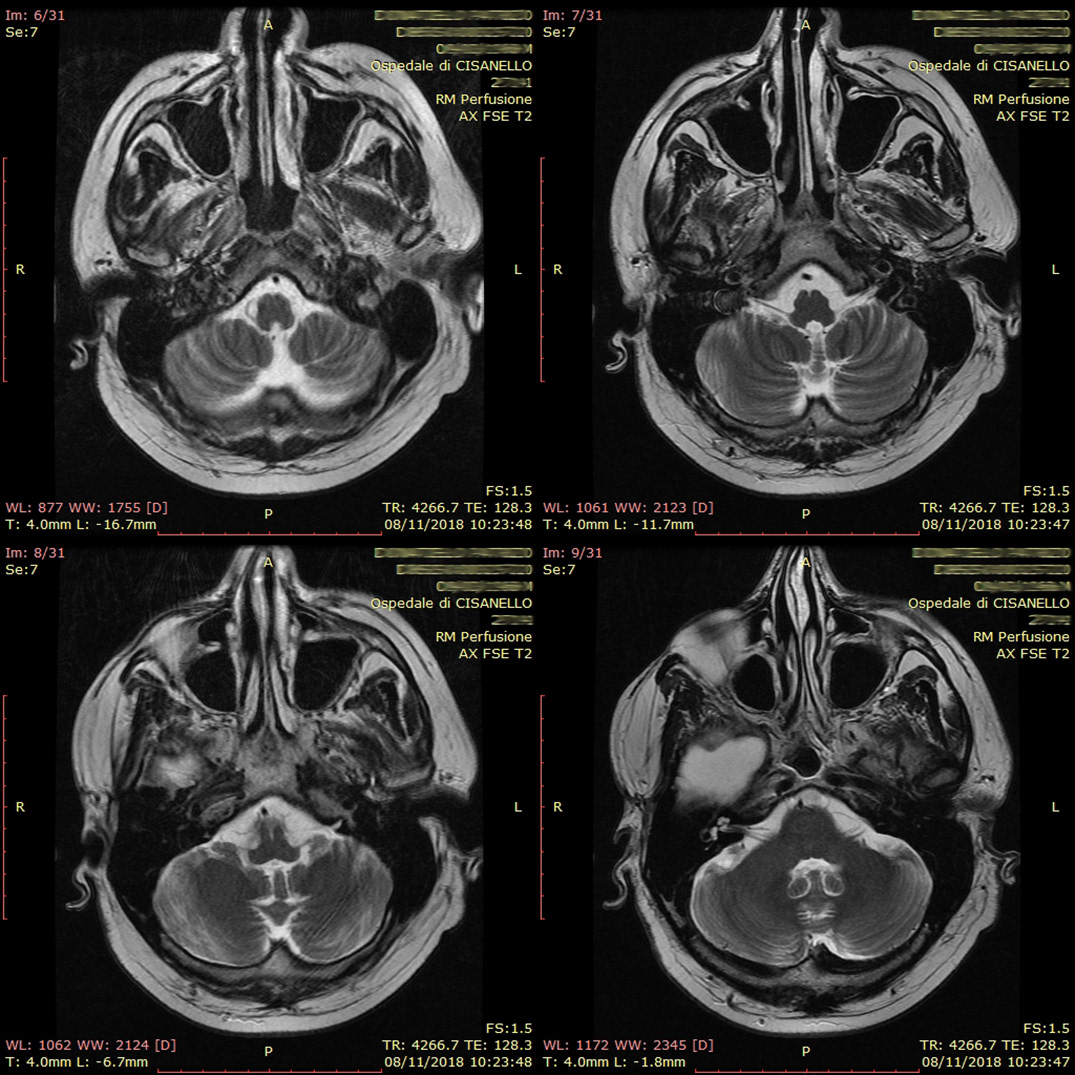

Mutor, which from Latin translates as "I have changed", is the anagram of "tumor", the cause of this change. In fact, in 2009 my father was diagnosed with a brain tumor that completely changed his life. Due to this disease he has lost more and more motor skills and memory.